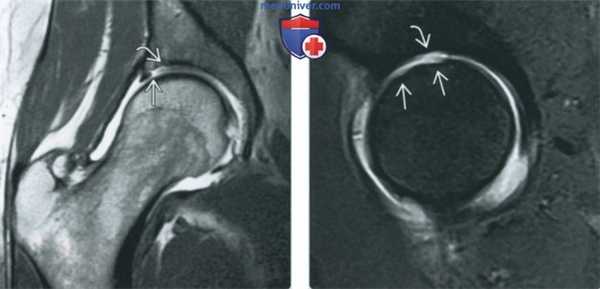

(Слева) МР-артрография в режиме PD FS, сагиттальный срез: визуализируется симптом печенья «Орео» - гиперинтенсивная жидкость между хрящом и субхондральной пластинкой кости, что соответствует отслоению хряща. Для постановки диагноза данные изменения должны выявляться как минимум на двух срезах в одной плоскости или на одном срезе, но в двух плоскостях.

(Справа) МР-артрография в режиме Т1ВИ FS, коронарный срез, этот же пациент: подтверждается отслоение суставного хряща, при этом медиальнее отмечается его глубокий дефект. Также выявляется разрыв суставной губы.

(Слева) МР-артрография в режиме Т1ВИ, коронарный срез: визуализируется затек контрастного препарата между отслоенным участком суставного хряща и субхондральной пластинкой кости. Целостность хрящевого лоскута нарушена с латеральной, но не с медиальной стороны.

(Справа) МР-артрография в режиме Т1ВИ FS, сагиттальный срез: отмечается истончение суставного хряща в верхнем отделе головки бедренной костив и прилежащем отделе вертлужной впадины. Причиной истончения хряща стала травма, полученная при игре в футбол.